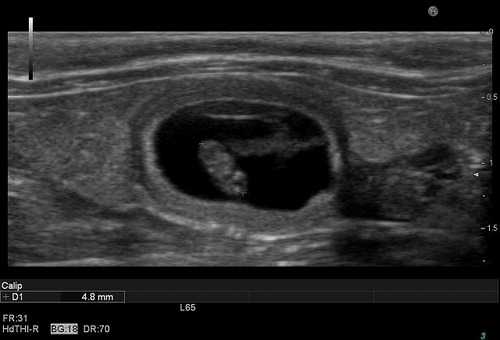

さらに詳しく、胎児の心臓の動きを観察してみると・・・

20100312090344.jpg